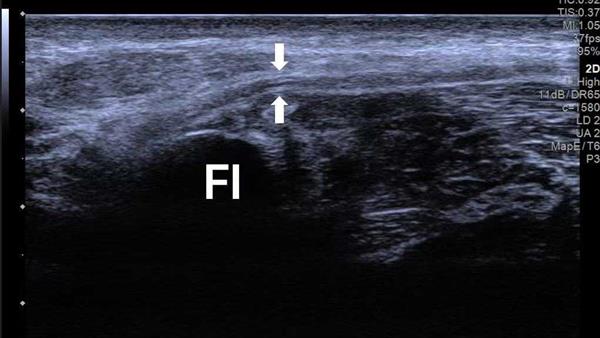

为进一步明确病情,团队为小彭开展了超声造影联合评估。首先通过弹性成像检测,初步判断神经组织硬度变化,图像中红色区域提示局部组织硬度增高,与腓总神经卡压部位高度相关。高频超声检查也清晰发现,受压的腓总神经局部增粗、回声变低,卡压点近端形成了梭形的膨大。

患者腓总神经超声扫查图;患者弹性检测区域图

声像图示:左侧腓总神经腓骨颈(FI)处变细,近端增粗,神经回声减低,神经外膜回声增强,神经束膜显示不清